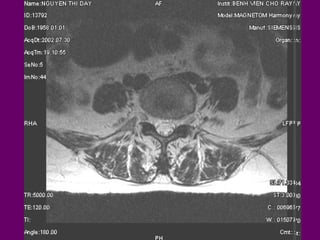

-Sagittal, Axial, Coronal

Sagittal, Axial, Coronal

AÛNH HÌNH AXIAL